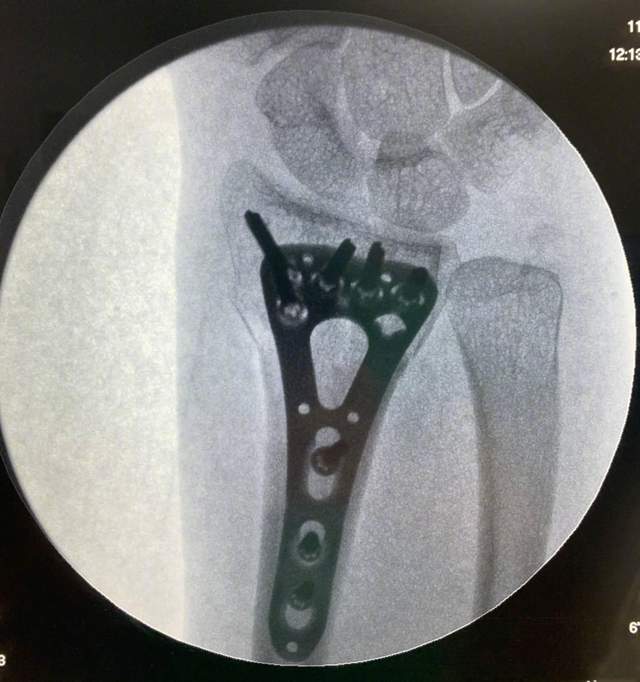

11月10号 , 吴京时隔两天再次晒出妻子谢楠的CT片子 , 桡骨里的钢板钢钉非常显眼 。

吴京配文称“二师妹成功把手中的钉耙像金箍棒一样变进了自己的身体里” , 后面还跟着一个竖大拇指的表情 , 虽是调侃语气 , 但也看得出他有夸谢楠勇敢的意思 。

像耙子的是钢板 , 钢钉通过它来固定骨头 , 在“骨折内固定术”的介绍中有图片 , 与谢楠的这个可以对应上 。

细数下来 , 谢楠这放入了八颗钢钉 , 触目惊心 , 难怪网友看一眼就觉得疼 。

8号的时候吴京曝出谢楠桡骨粉碎性骨折 , 还说出了手术时间 , 才手术一天他就晒出了谢楠的钢钉照 , 一部分原因或许是想让关心他们的人能够早点放心 , 报个平安 , 毕竟晒出来就意味着手术成功 。